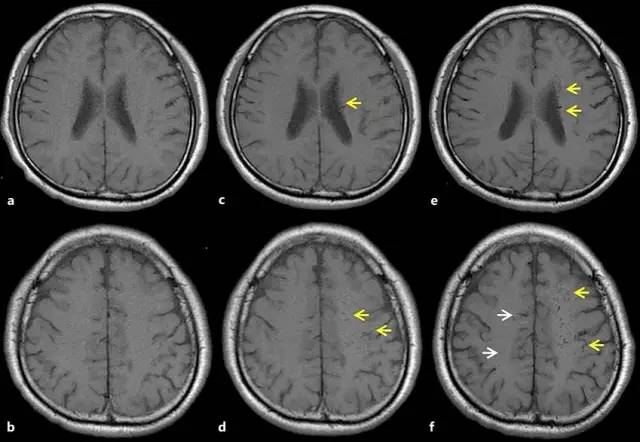

1年后,患者突然出现右侧肢体无力、言语障碍和感觉缺失。此时的MRI和MRA未见明显责任病灶,脑电图同样没有显示癫痫的证据。患者被怀疑脑缺血并接受了抗血小板治疗。本次入院后,患者未再发生震颤,但在入院后第5天,患者右侧肢体无力出现恶化。此时复查MRI,显示从额叶和顶叶的深部髓质静脉到浅表髓质静脉可见多发扩张(图2),此外还可看到围绕这些扩张静脉的脑白质变化。相比之下,双侧基底节、丘脑、脑干和小脑未见显著异常。MR静脉造影证实为上矢状窦前部闭塞(图3)。

图2 轴位T1WI显示左侧额叶/顶叶的浅表髓质静脉的逐渐扩张(黄色箭头)及右侧额叶/顶叶的浅表髓质静脉扩张(白色箭头)

a、b:首次就诊时的检查;c、d:住院时的检查;e、f:症状恶化时的检查